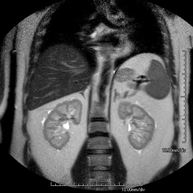

Prueba diagnóstica no invasiva que consiste en la obtención de imágenes de alta definición anatómica de ambos riñones mediante el empleo de un campo electromagnético y ondas de radio (con un emisor y un receptor). No utiliza radiación ionizante. Se realiza para estudiar cualquier lesión localizada en ambos riñones. Normalmente se requiere el uso de contraste paramagnético (Gadolinio) para caracterizar las lesiones. - RM Glándulas Suprarrenales

- URO-RM

Prueba diagnóstica no invasiva que consiste en la obtención de imágenes de alta definición anatómica del sistema urinario mediante el empleo de un campo electromagnético y ondas de radio (con un emisor y un receptor). No utiliza radiación ionizante. Requiere el uso de contraste paramagnético (Gadolinio) que se excretará por el sistema urinario y nos permitirá obtener imágenes en 2D y 3D. - RM Próstata